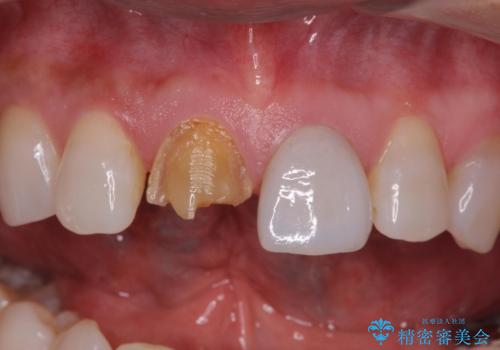

- 前歯につけていたべニアが取れたとのことで来院された患者様です。

より脱離リスクの低いクラウンでの修復を行います。

取れていない方のべニアも周囲の歯と色調が合っていなかったため、一緒にやり替えました。